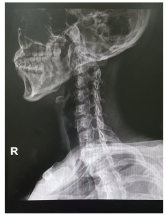

목디스크 증상 원인 치료방법 등 목 디스크 관련 정보에 대해 알아보도록 하겠습니다. 목디스크는 인간의 척추 중 경추부나 흉추부에 위치한 디스크(틀니)가 변형되어 생긴 질환으로, 경추부의 경우 목의 통증, 저림 혹은 근육 경련, 어깨와 팔의 통증, 감각상실 등이 나타나며, 흉추부의 경우 흉부의 통증, 등의 통증 등이 나타납니다. 보통은 원인불명성으로 인한 자연적인 회복을 기다리는 것이 가장 좋으며, 통증이 심한 경우 보조적으로 항통제나 근육 이완제 등을 사용합니다. 만약 압력이 심한 경우 수술이 필요할 수 있습니다.예방법으로는 바른 자세 유지와 체중 조절, 충분한 운동, 목과 등의 근육 강화 등이 있습니다.

1. 목 통증: 목 디스크의 가장 흔한 증상으로, 목이 뻐근하고 아프며 움직일 때 통증이 심해집니다. 통증은 어깨나 팔, 손가락까지 전도될 수 있습니다.

2. 근육 경직: 목 디스크로 인해 목 주변의 근육이 긴장되고 경직되어, 목을 돌리거나 숙이기 어렵습니다. 근육 경직은 통증을 더욱 악화시킬 수 있습니다.

3. 감각 장애: 목 디스크로 인해 신경이 압박되면, 팔이나 손가락에 저림감이나 마비감이 생길 수 있습니다. 감각 장애는 일시적일 수도 있고, 지속적일 수도 있습니다.

4. 두통: 목 디스크로 인해 목과 머리 사이의 혈류가 방해되면, 두통이 발생할 수 있습니다. 두통은 보통 뒤통수나 이마에 나타나며, 움직임에 따라 심해지거나 가라앉을 수 있습니다.

5. 현기증: 목 디스크로 인해 척추동맥이 압박되면, 현기증이 발생할 수 있습니다. 현기증은 일어서거나 누워있을 때 갑자기 나타날 수 있으며, 균형감을 잃거나 구역질을 유발할 수 있습니다.